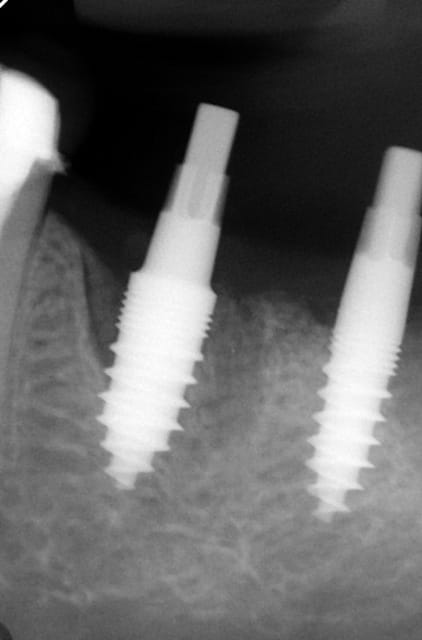

Maintenant concernant la demande de scans : je poste ce cas, une patiente vient me voir avec son scan car elle a consulté d'autres "spécialistes" et on lui refuse la pose d'implant secteur 4 où alors avec greffe préalable..Ca se discute..pas de temps à perdre je sais faire autrement..

Avec la chir trans gingivale technique MIMI ( Oui..un post sur la technique bientôt ..) j'ai pu placer deux 3,5/8mm..aurai je eu le meme résultat avec un lambeau..j'en doute..Les couronnes sont en titane. Recul clinique 2 ans ras. Simple efficace rapide moins onéreux satisfaisant pour le praticien et la patiente..